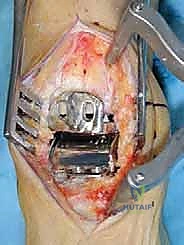

تُجرى العملية عادة تحت التخدير النصفي أو العام، وتستغرق حوالي الساعتين إلى ثلاث ساعات. الدقة هنا تقاس بالمليمترات وأجزاء الدرجة الزاوية.

1. الشق الجراحي والوصول للمفصل

يقوم الجراح بإجراء شق أمامي طولي (Anterior Approach) في منتصف الكاحل. يتم إبعاد الأوتار والأوعية الدموية والأعصاب بعناية فائقة (هنا تتجلى أهمية مهارات الجراحة الدقيقة التي يمتلكها الدكتور هطيف) للوصول إلى محفظة المفصل.

2. إزالة الزوائد العظمية وتحرير المفصل

يتم إزالة النتوءات العظمية (Osteophytes) التي تسبب الألم وتحد من الحركة، وتحرير الأنسجة المتليفة لاستعادة المرونة الأولية للمفصل.